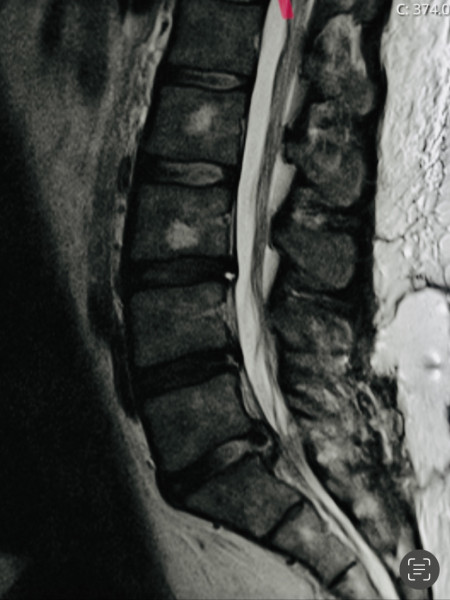

MrOllivander · 30/04/2022 11:44

Yeah I'm pretty sure (in my limited!) experience that's a surgery needed

This is mine and it just got bigger and bigger

Could this be cauda equina